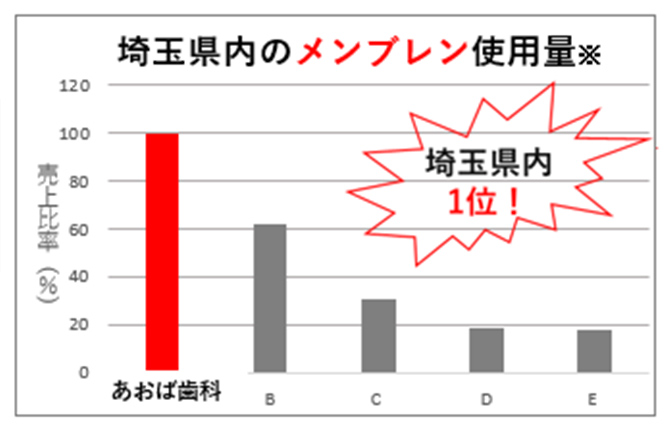

埼玉県内で

昨年も高い

再生医療実績(2025年)